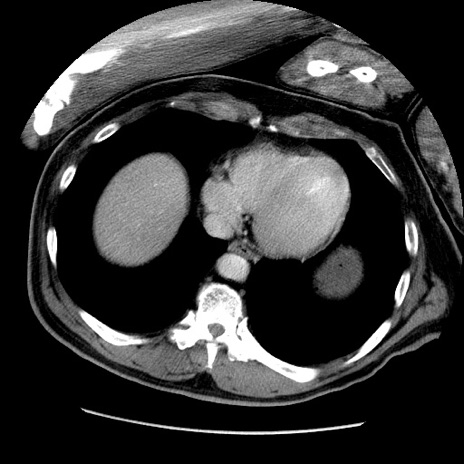

症例22(横断像)

【症例】50歳代男性

【主訴】腹痛

【現病歴】AVMからの被殻出血のため回復期リハ病棟入院中。 本日午後3時頃急に下腹部痛が出現した。

【既往歴】AVM、被殻出血、虫垂炎、高血圧

【身体所見】意識晴明、左半身不全麻痺、会話の理解は良好、36.5°C、腹部:膨隆、全体に板状硬、下腹部正中に圧痛点あり、反跳痛-、筋性防御不明、右下腹部にope scar

【データ】WBC 9400、CRP 0.06